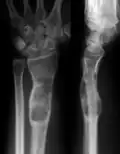

| X-ray image showing enchondromas localized in the lower part of the radius of a 7-year-old girl with Ollier disease. | |